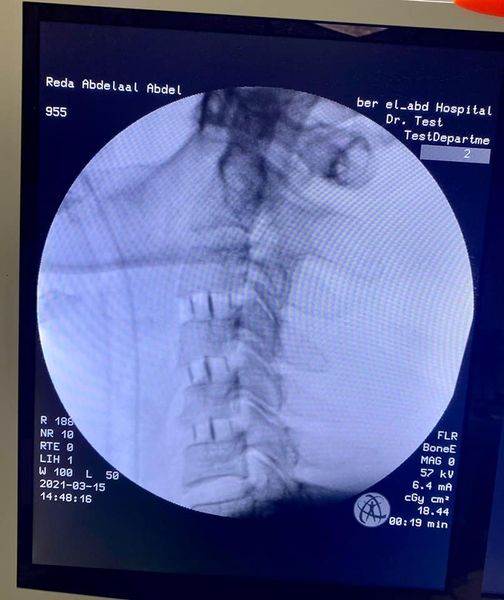

وأعلن الدكتور تامر حمدى مدير إدارة المستشفى ( فى بيان ) أن الفريق الطبي قام بمجرد وصول المريض الى المستشفى باجراء جراحة عاجلة .. حيث تم استئصال ثلاثة غضاريف عنقية أمامية .. مع تركيب أقفاص كربونية للمريض البالغ من العمر ٤١ عاما ، وقد تحسنت حالته وأصبح قادرا على الحركة وتوقف الخذلان .. مشيرا الى أن جراحات الفقرات العنقية هى الأولى من نوعها بمستشفى بئر العبد المركزى ، وهى من أدق جراحات المخ والأعصاب والعمود الفقرى على الاطلاق.

وأضاف أن الطاقم الطبي الذي أجرى الجراحة للمريض ضم كل من : الدكتور أحمد مأمون سرحان مدرس مساعد وأخصائى جراحة المخ والأعصاب والعمود الفقرى بجامعة الزقازيق ، الدكتورة ياسمين حسن حمدى مدرس مساعد وأخصائى التخدير بطب القصر العينى فى جامعة القاهرة .. الى جانب فريق المستشفى وطاقم التمريض وفنيى الاشاعة